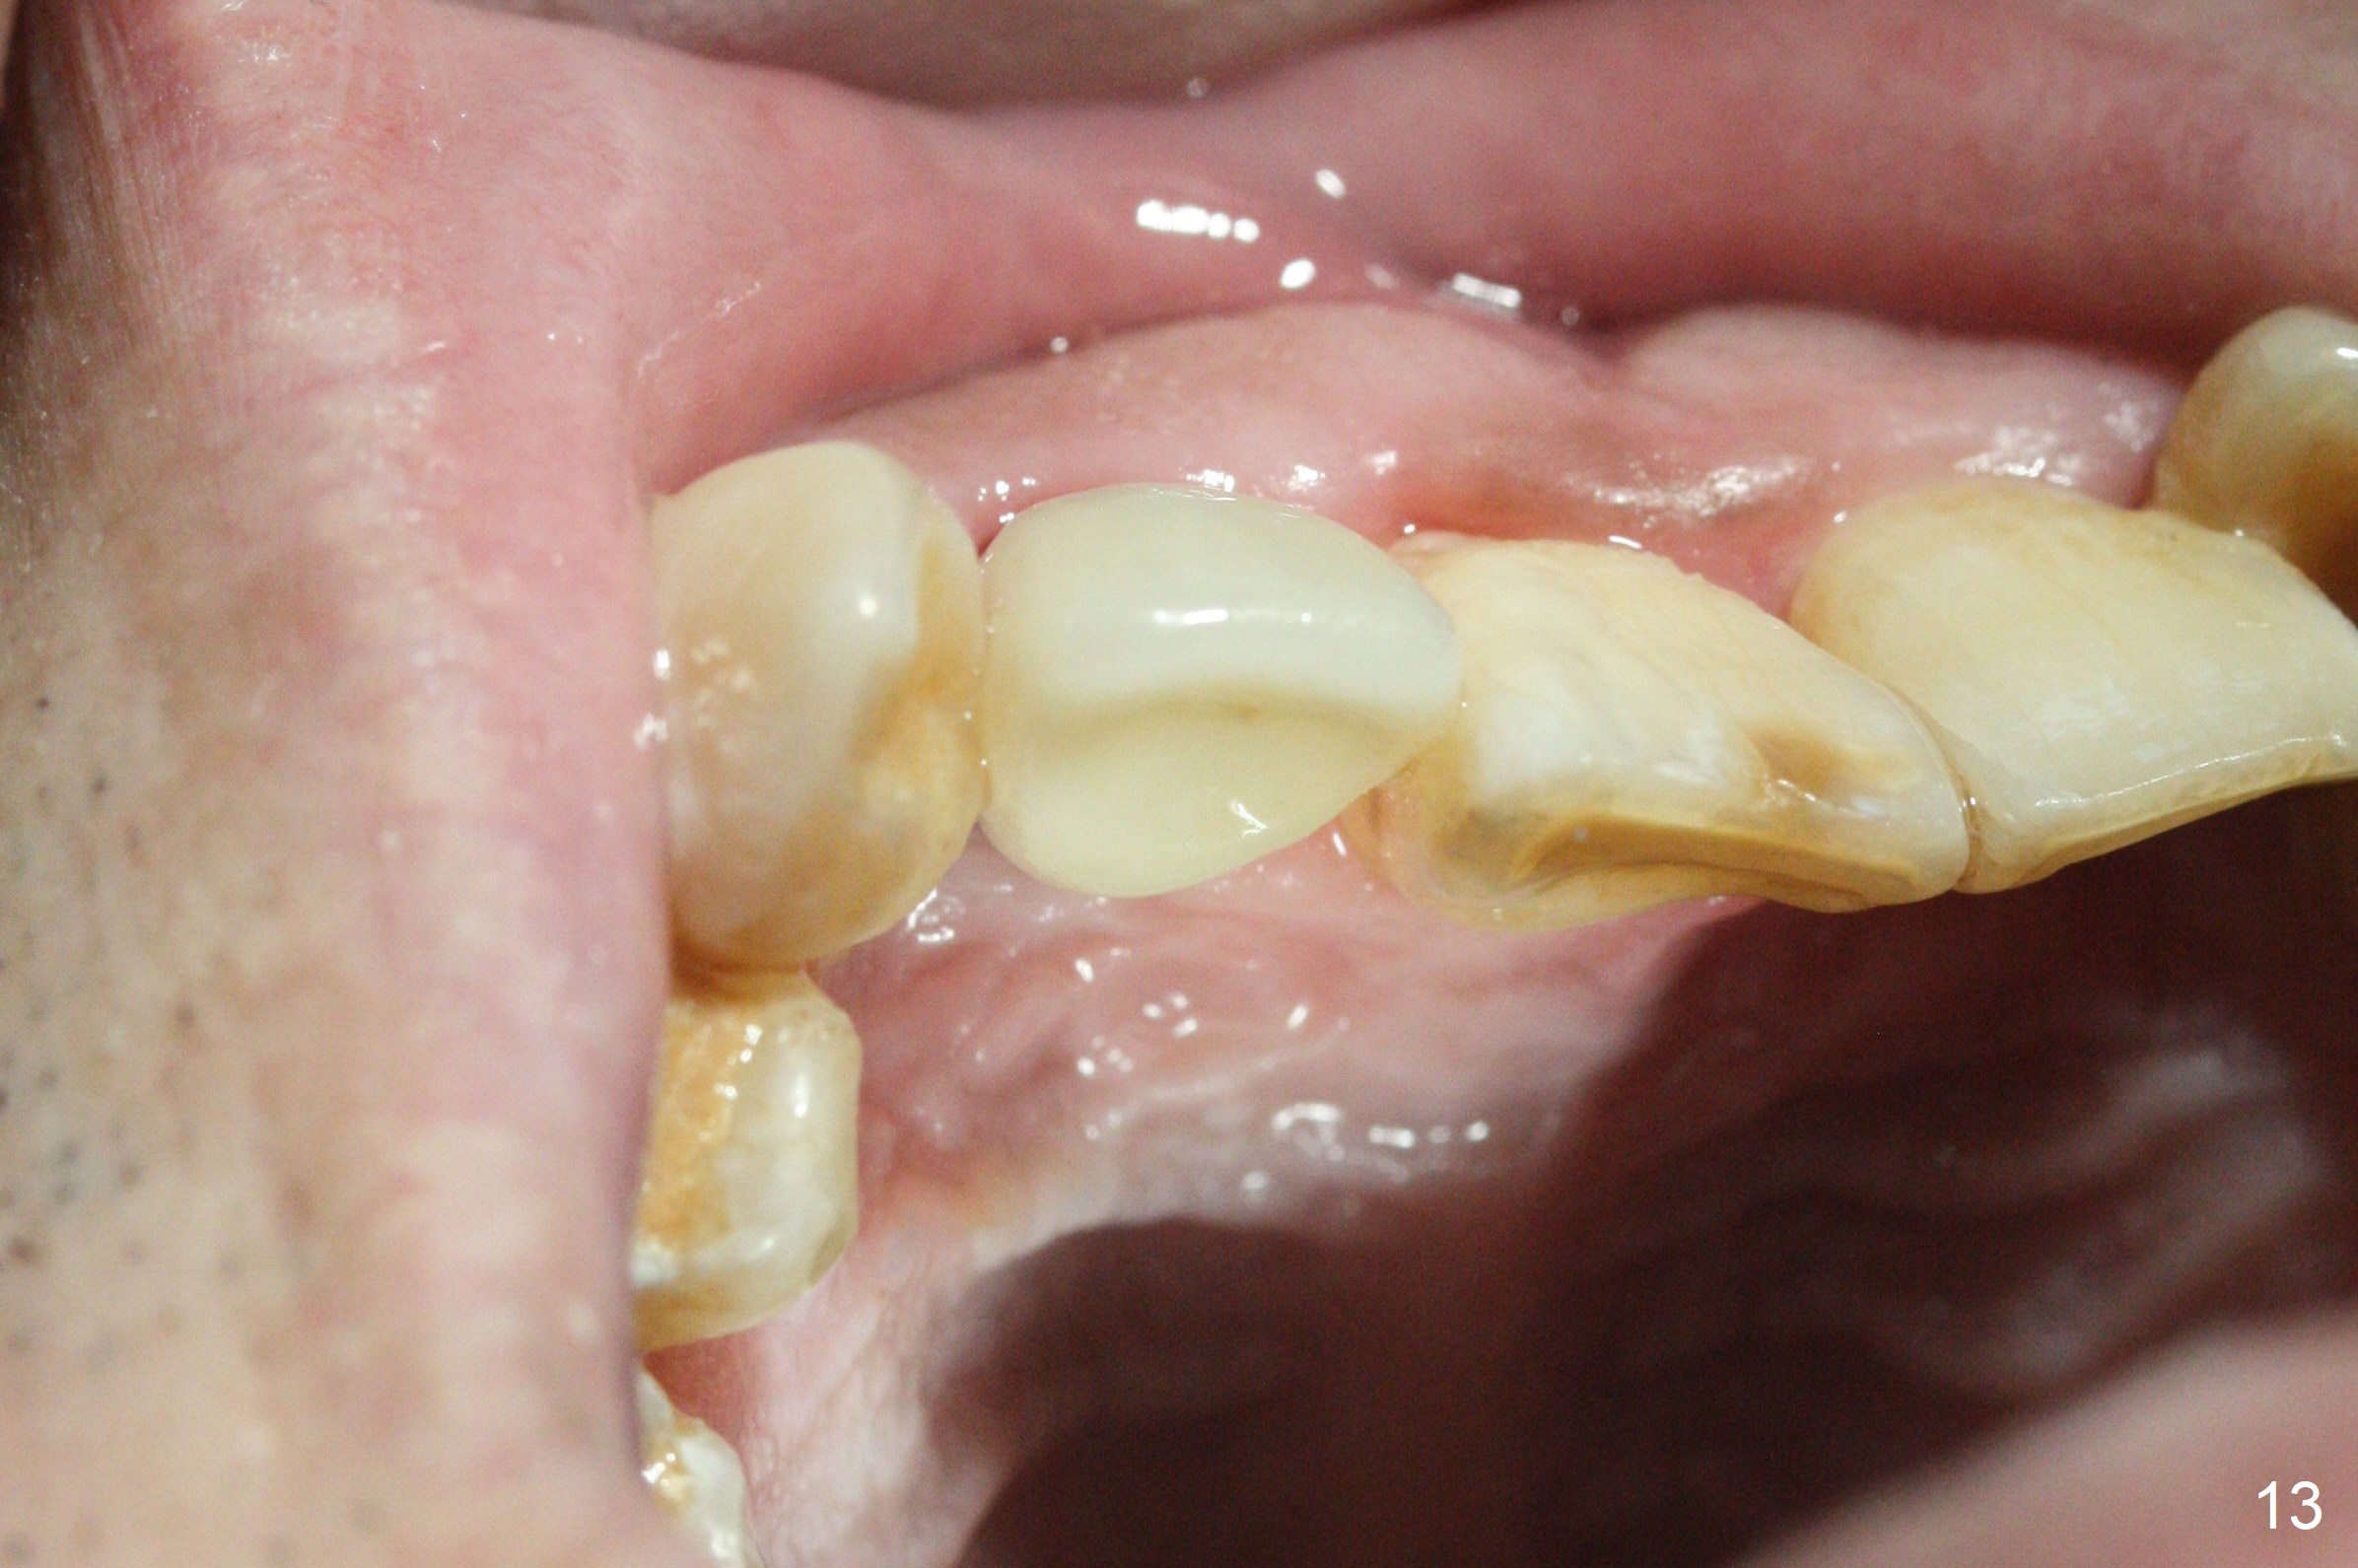

Access to the fractured root is limited after the crown is removed (Fig.1 *). Note the buccally-positioned tooth #10. After explanation the patient accepts in advance the possibility of the similar or same position of the restoration at #7.

Sixteen days postop, the patient is doing fine, although the labial fistula has not disappeared (Fig.8 <). The detached distolabial papilla is healing (Fig.9 *) with mild bone graft exposure (^). The lacerated distopalatal papilla is also healing (Fig.10 *). These complications are related to flap surgery. The apical portion of the socket appears to have reduced 4 months postop (Fig.14). When the definitive restoration is delivered 5 months postop, there is gingival recession, including the distal of #8 (Fig.11 arrows, which is expected to improve over time) due to flap surgery. The labial plate collapse is minimal (Fig.12 *), while the palatal laceration (Fig.10) has healed (Fig.13). When the patient returns 1.5 years post cementation, there is increased bone density next to the coronal portion of the implant, equivalent to the bone graft (Fig.15 *). The fistula is absent (Fig.16). The crestal bone loss remains 2.5 years post cementation (Fig.17 *), although there is no sign of periimplantitis (magnification). Oral hygiene is poor. There is no change in the soft (gingival recession; data not shown) or hard tissues 3 years 8 months post cementation (Fig.18).